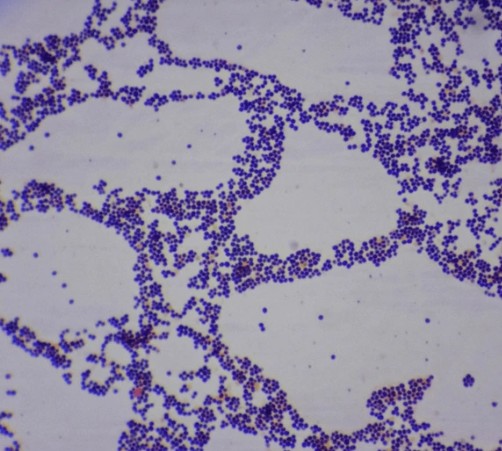

황색포도알균은 현미경으로 보면 지름 약 0.5~1.5㎛ 크기의 둥근 공 모양 세균이 포도송이처럼 무리지어 배치된 특징적인 형태를 지닙니다.

• 그람양성균

그람염색 시 보라색으로 염색되며, 두꺼운 세포벽을 갖고 있습니다.